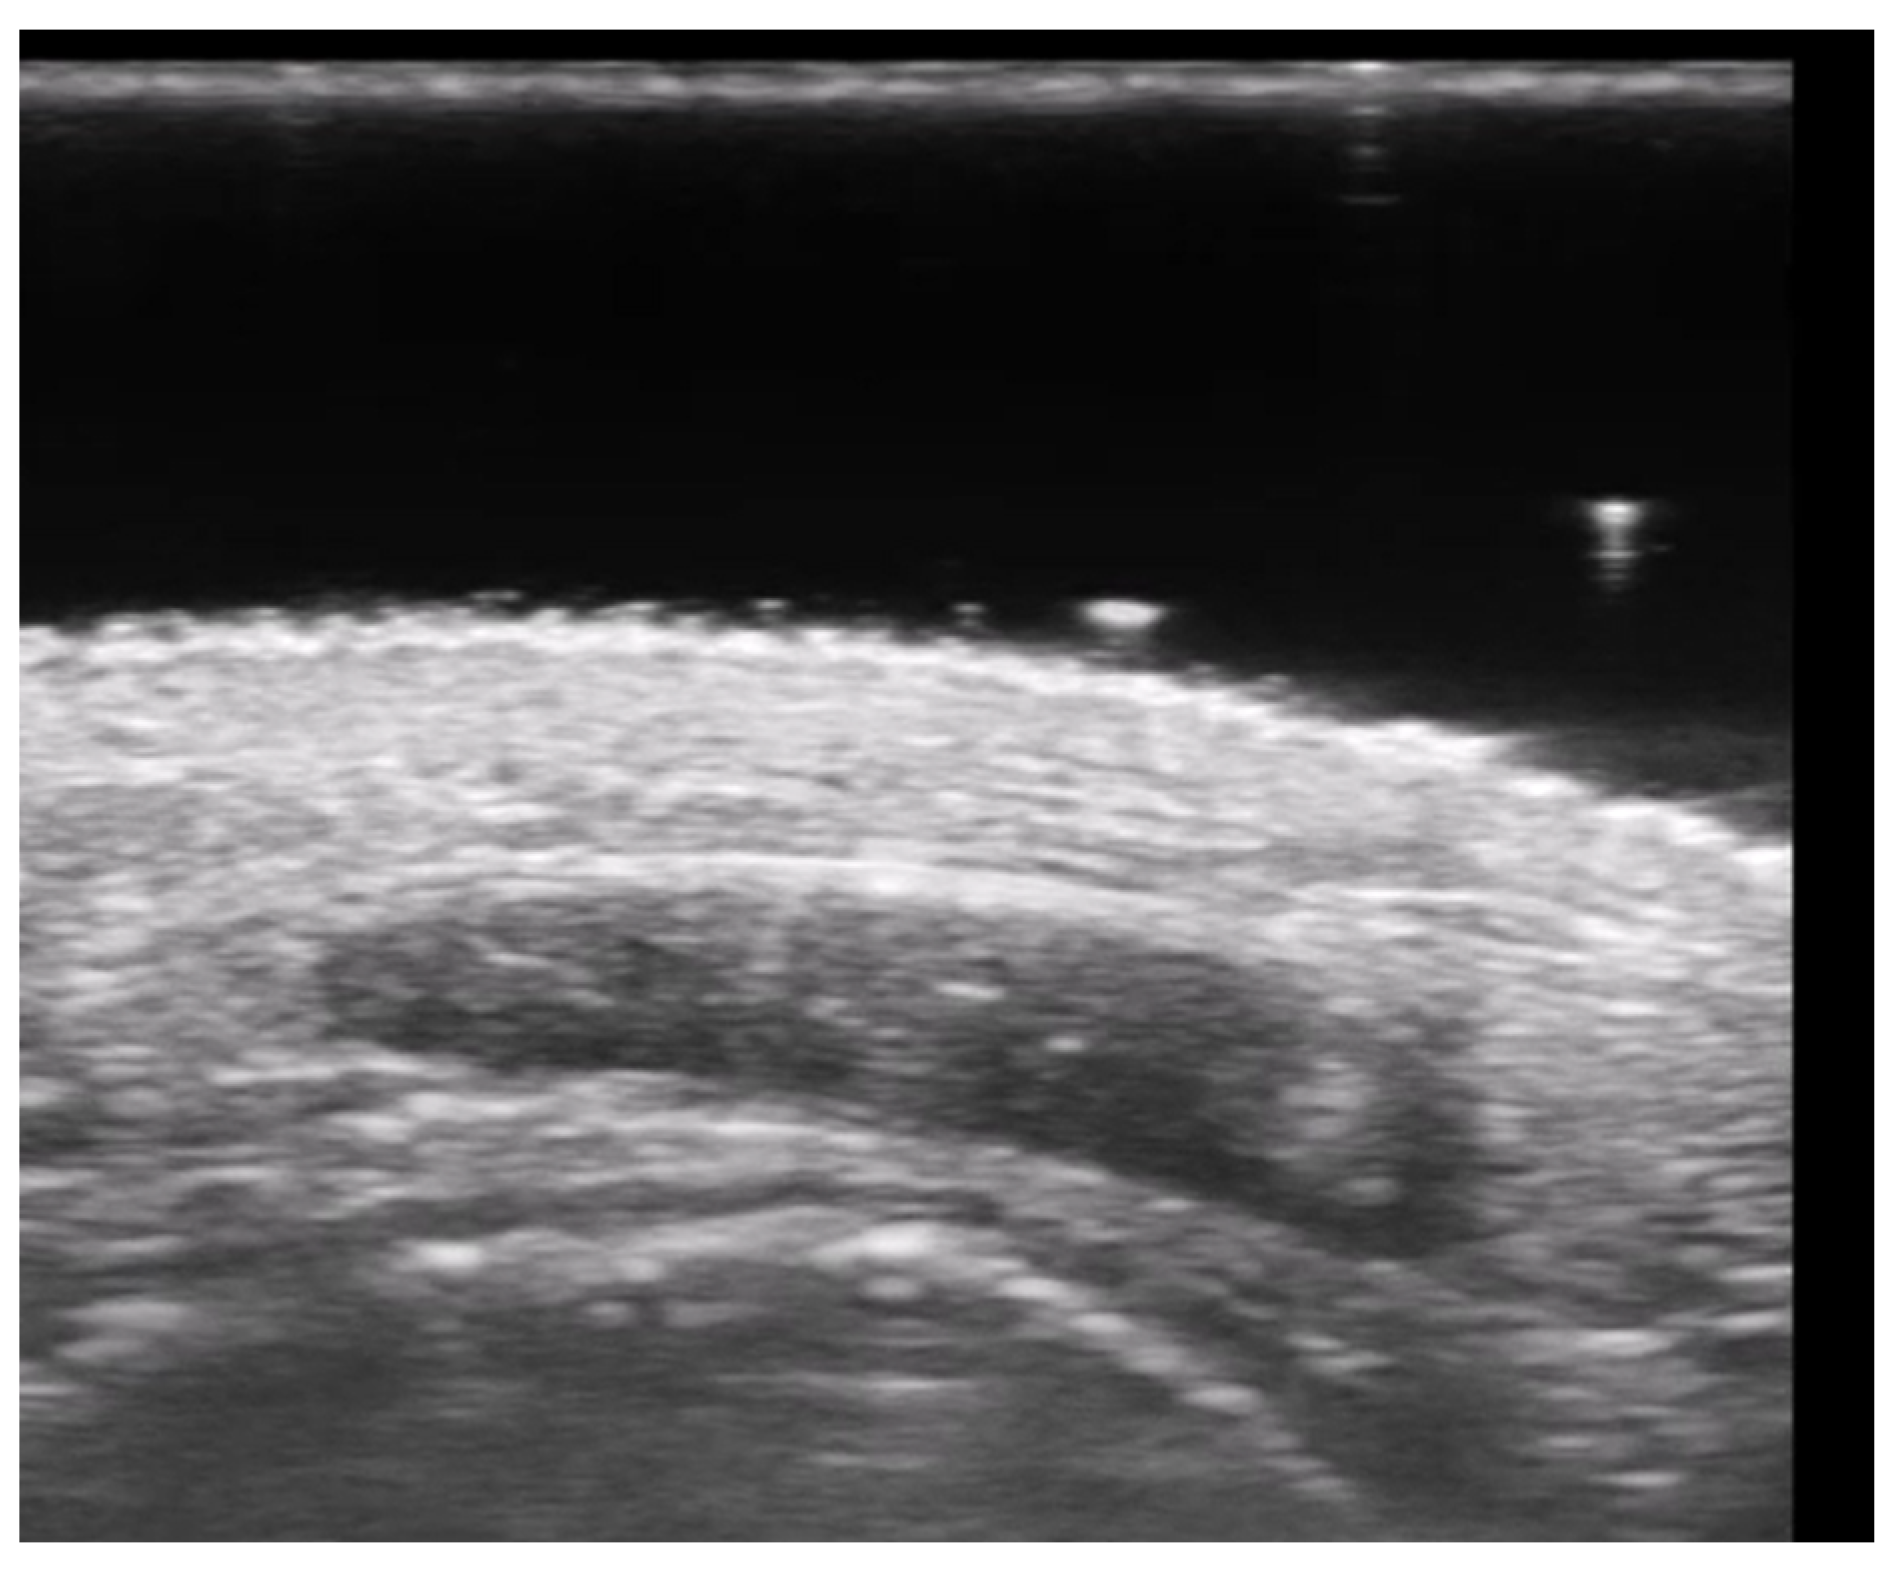

- Negrutiu, M.; Danescu, S.; Popa, T.; Focsan, M.; Vesa, S.C.; Szasz, F.; Baican, A. Imaging Approach in the Diagnostics and Evaluation of the Psoriasis Plaque: A Preliminary Study and Literature Review. Diagnostics 2024, 14, 969. [Google Scholar] [CrossRef] [PubMed]